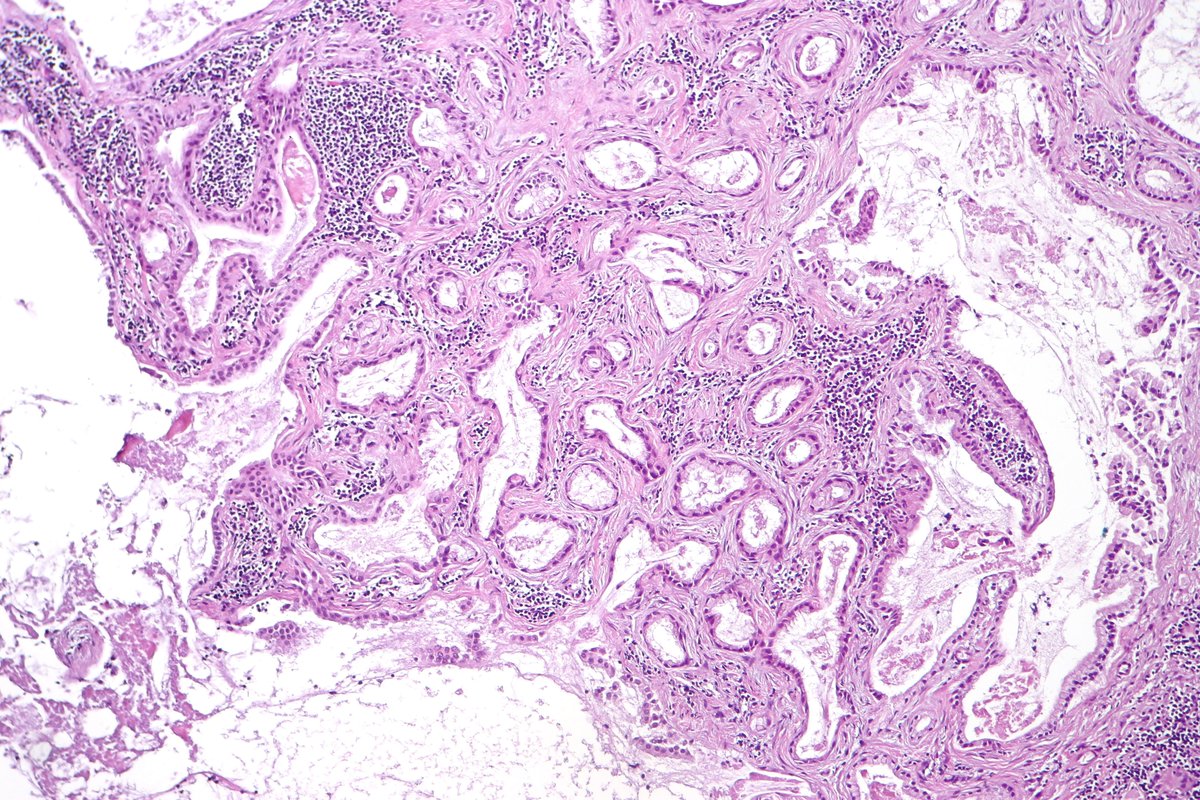

Pancreatobiliary-type adenocarcinoma lymph node metastasis showing well-formed, irregular glands associated with desmoplastic stroma. #pathology #GIPath